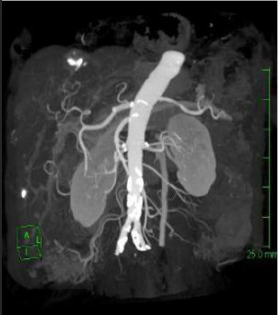

在整體的影像鏈環節進行了改進确保高清晰的圖像。實現了圖像的各向同性,任意方向的 MPR 圖像具有相同的圖像質量。